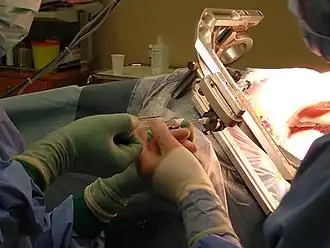

A biopsy is a medical test commonly performed by a surgeon, an interventional radiologist, or an interventional cardiologist. The process involves the extraction of sample cells or tissues for examination to determine the presence or extent of a disease. The tissue is then fixed, dehydrated, embedded, sectioned, stained and mounted[1] before it is generally examined under a microscope by a pathologist; it may also be analyzed chemically. When an entire lump or suspicious area is removed, the procedure is called an excisional biopsy. An incisional biopsy or core biopsy samples a portion of the abnormal tissue without attempting to remove the entire lesion or tumor. When a sample of tissue or fluid is removed with a needle in such a way that cells are removed without preserving the histological architecture of the tissue cells, the procedure is called a needle aspiration biopsy. Biopsies are most commonly performed for insight into possible cancerous or inflammatory conditions.

When intact removal is not indicated for a variety of reasons, a wedge of tissue may be taken in an incisional biopsy. In some cases, a sample can be collected by devices that "bite" a sample. A variety of sizes of needles can collect tissue in the lumen (core biopsy). Smaller diameter needles collect cells and cell clusters, fine needle aspiration biopsy.[6]

| Lung | Biopsies of the lung can be performed in a variety of ways depending on the location. |